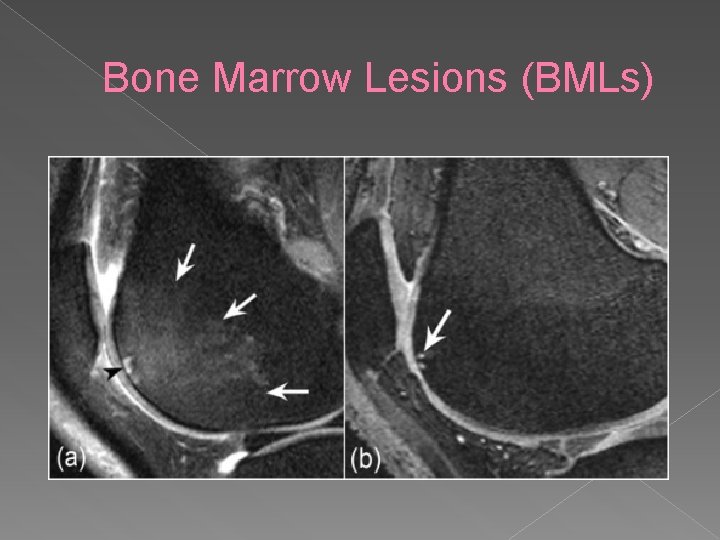

Bone Marrow Lesions (BMLs)